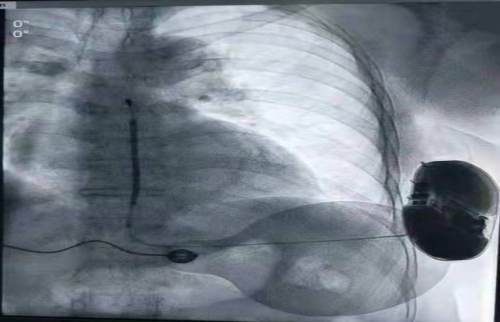

综合以上因素,张志辉团队经过充分的术前讨论后,于9月17日为患者成功植入SICD。术前经过X线透视一次,确定最佳感知位置,并用记号笔标识,关闭射线。手术在无射线的情况下,50分钟顺利结束,并且术中进行诱颤测试。采用50Hz,200mA交流电方式诱发室颤,S-ICD正确识别,经首次65J除颤成功,标准着SICD正式的成为患者预防猝死的利器,同时也标志着湖南省首台SICD植入成功。